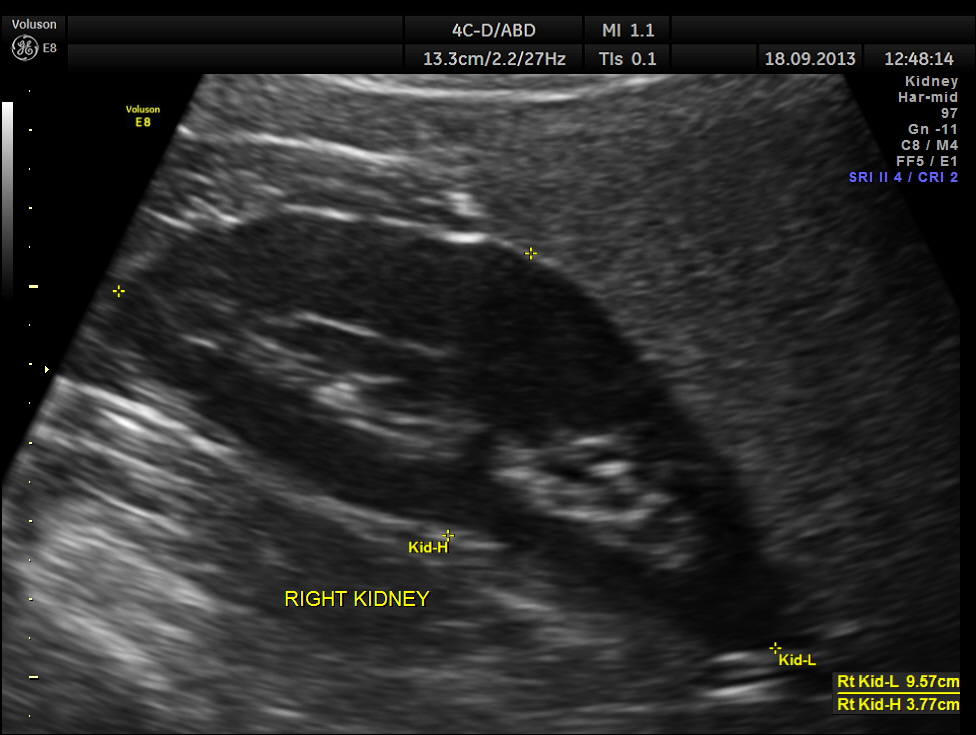

Ultrasound revealed normal liver, gall bladder, pancreas, spleen ,post menopausal shrunk uterus and normal right kidney.